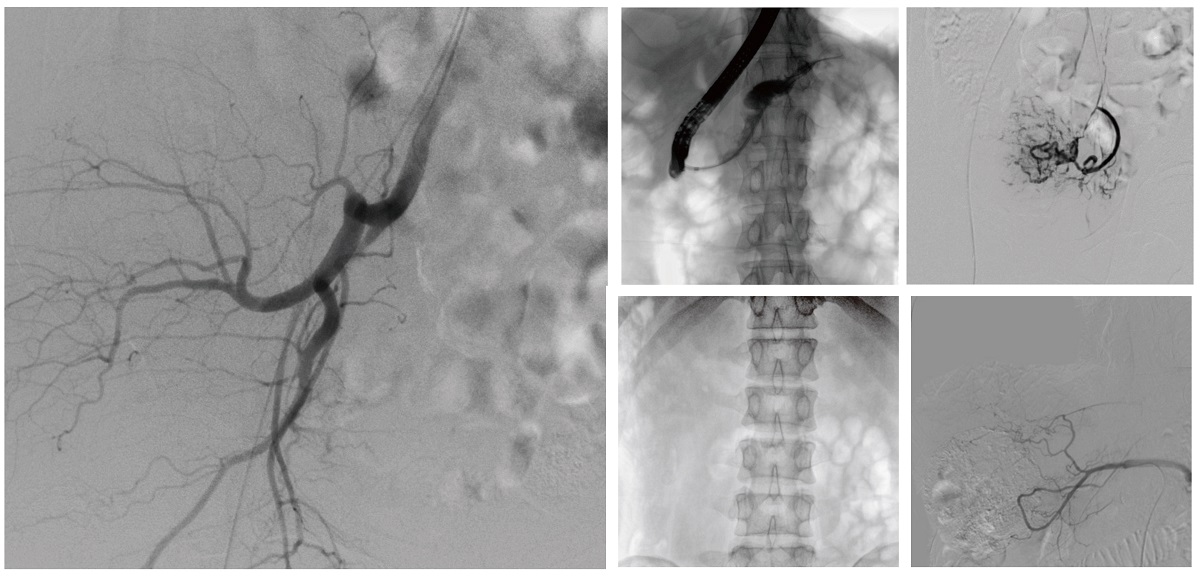

醫(yī)院引進(jìn)的普愛醫(yī)療移動式平板介入中C,其高清成像能力覆蓋骨科、介入科、泌尿外科、婦產(chǎn)科等多科室,能夠滿足介入微創(chuàng)手術(shù)的多樣化需求。

設(shè)備的移動式設(shè)計(jì),無需對現(xiàn)有手術(shù)室進(jìn)行改造,適合高負(fù)荷手術(shù)量或應(yīng)急情況下的靈活部署。如在急診介入手術(shù)中,該設(shè)備能迅速響應(yīng)需求,為醫(yī)生提供實(shí)時(shí)影像支持,提升搶救效率。